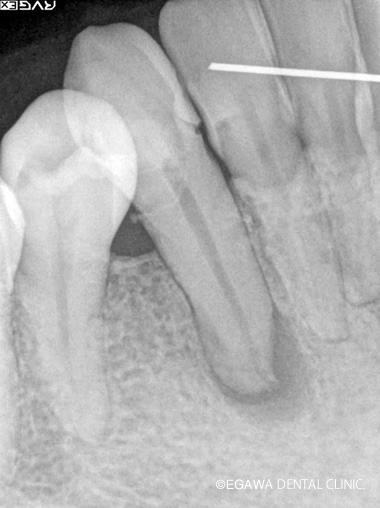

症例2

術前

術後